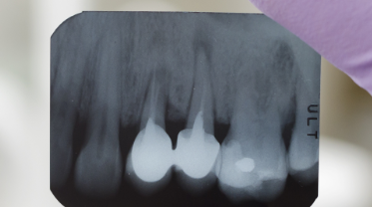

Oral diagnoz ağız içinde oluşabilecek herhangi bir hastalığın teşhis edilmesini sağlayan radyolojik tetkiktir. Hastalara müdahale edilmeden ilk yapılan işlem oral diagnoz ve dental radyolojidir. Oral diagnoz ve dental radyoloji uzman diş hekimleri tarafından ilk muayene, ağzın genel yapısını ve çeneyi panoramik olarak görüntüleme biçimidir. Bu tetkik sonucunda hastaya uygulanması gereken tedavi planı oluşturulur ve hasta tedaviye alınır. Dental radyoloji ile yalnızca dişlerin teşhisi değil 20 yaş dişi, diş eti sorunları, çene kemiği, yanak, damak gibi birçok dokunun görüntülenmesi sağlanır. Oral diagnoz ve radyoloji tetkikinde yalnızca ağız içi dokuları değil bunun dışında kronik hastalıklardan olan diyabet ve behçet hastalıkları da teşhis edilir.